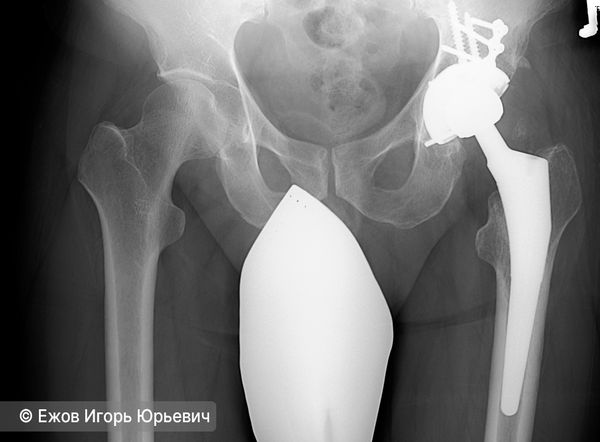

Эндопротезирование тазобедренного сустава

При развитии артроза 3-й стадии показано оперативное лечение — тотальное эндопротезирование тазобедренного сустава, при котором заменяют сразу обе суставные поверхности: головку бедренной кости и вертлужную впадину. Даже при развитии осложнений такая операция показывает хорошие результаты: она облегчает боль, восстанавливает опорность ноги и улучшает качество жизни.

Тотальное эндопротезирование